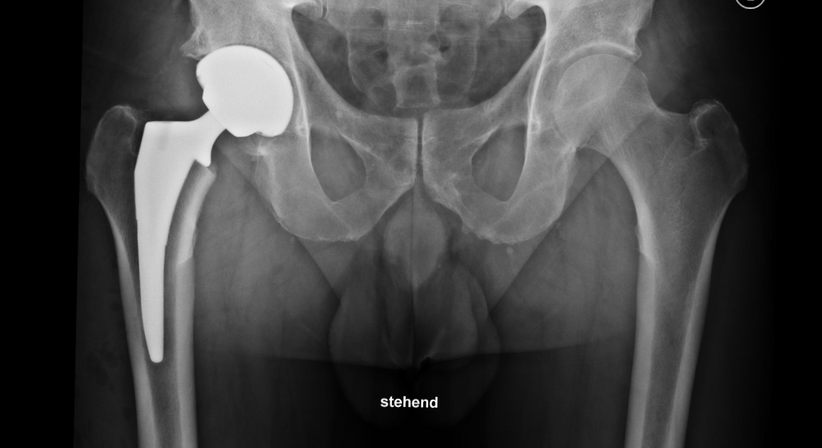

Eine Hüftprothese ersetzt das natürliche Hüftgelenk durch Komponenten aus Metall (Titan bzw. Chrom-Kobalt-Molybdän-Legierungen), Keramik und Kunststoff (Polyethylen). Das künstliche Hüftgelenk besteht aus einer Pfanne, einem Pfannen-Einsatz (Inlay), einem Schaft und einem Hüftkopf.